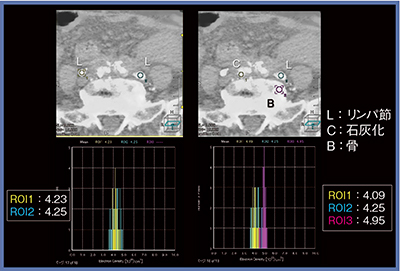

実効原子番号と電子密度による物質弁別

当院では,DECTの物質弁別について,実効原子番号(Effective Z)と電子密度(Electron Density)の検討も行った。当院で使用したリピオドール,ヨード造影剤,ガドリニウム造影剤について体外ファントムで解析を行った結果,実効原子番号と電子密度は図6のとおりとなった。実際に実効原子番号でリピオドールを弁別できるか検討したところ,リンパ管造影ではリピオドールの沈着を表しており,また,リンパ節のリピオドール沈着と石灰化,骨のそれぞれの実効原子番号を見ると,分離は可能だと思われる(図7)。一方,電子密度ではリピオドールと石灰化,骨のプロットが重なる部分があり,弁別は困難だと言える(図8)。

このことから実効原子番号によるリピオドール弁別は可能と思われたが,ROIが小さい小病変では測定が困難で,集積の程度により測定値にバラツキがあり,また,体内測定時のゴールドスタンダードが存在しないという問題がある。